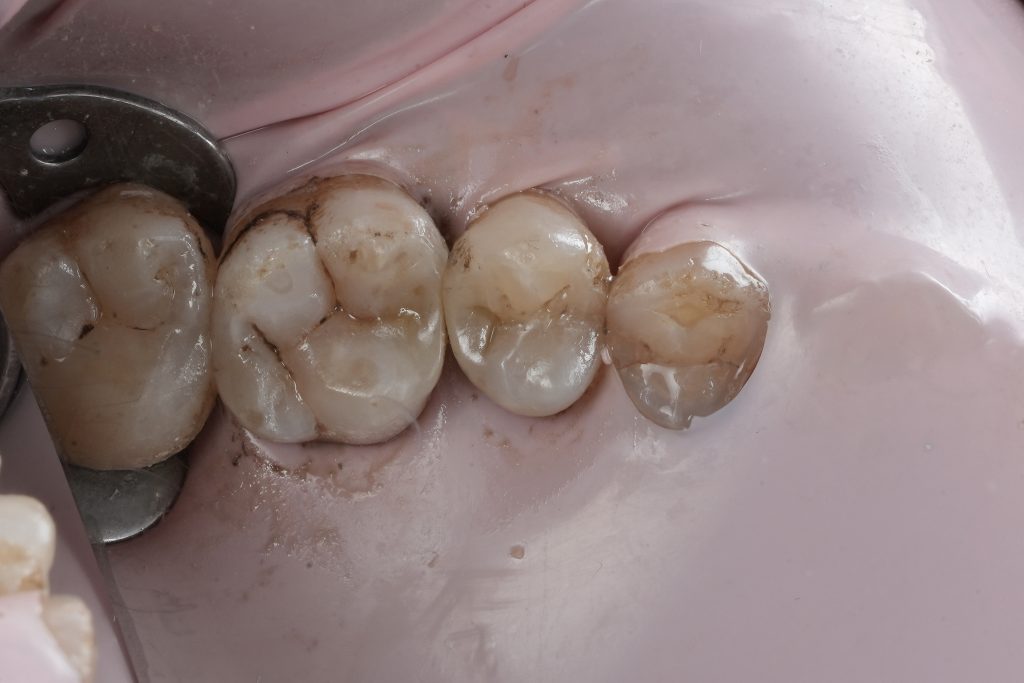

Class II Composite Restoration Under Rubber Dam Isolation in a Vital Tooth

Restoring a Class II cavity is not simply about filling a defect; it is about re-establishing proximal anatomy, contact integrity, and occlusal harmony while preserving pulpal vitality. This case demonstrates a protocol-driven Class II composite restoration performed under absolute rubber dam isolation, using controlled caries removal and precise matrix management to rebuild natural proximal contour and contact predictably.

Clinical examination revealed a proximal carious lesion affecting a vital posterior tooth. Pulp vitality tests were positive, and no signs of irreversible pulpal pathology were present. Radiographic assessment confirmed caries limited to dentin without pulpal involvement.

Isolation

Absolute rubber dam isolation was established prior to operative procedures. This ensured:

- A dry, contamination-free field

- Accurate shade perception

- Improved adhesive performance

- Enhanced visibility of cavity margins

Isolation was maintained throughout the procedure without compromise.

Cavity Preparation and Caries Removal

Caries removal was performed conservatively, focusing on complete elimination of infected dentin while preserving sound tooth structure. The cavity design respected enamel margins and avoided unnecessary extension.

Special attention was given to the gingival margin to ensure clean, accessible bonding surfaces.